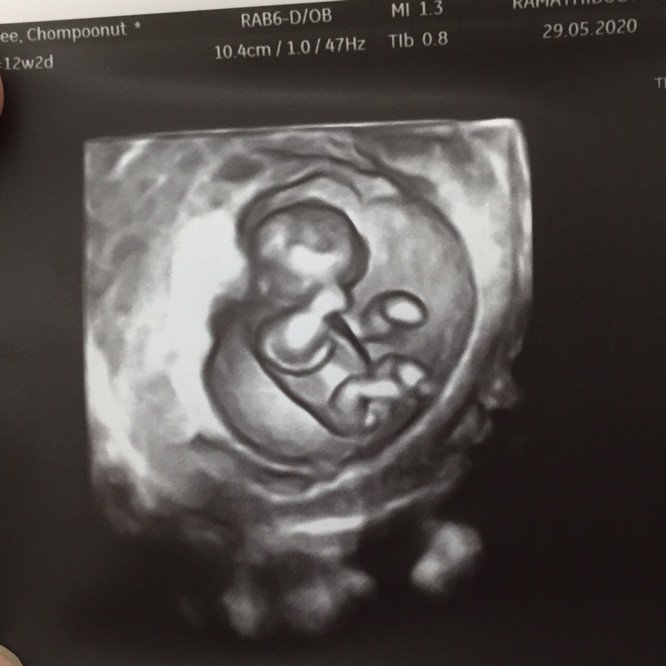

12 วีค ผู้หญิง80% ค่ะ